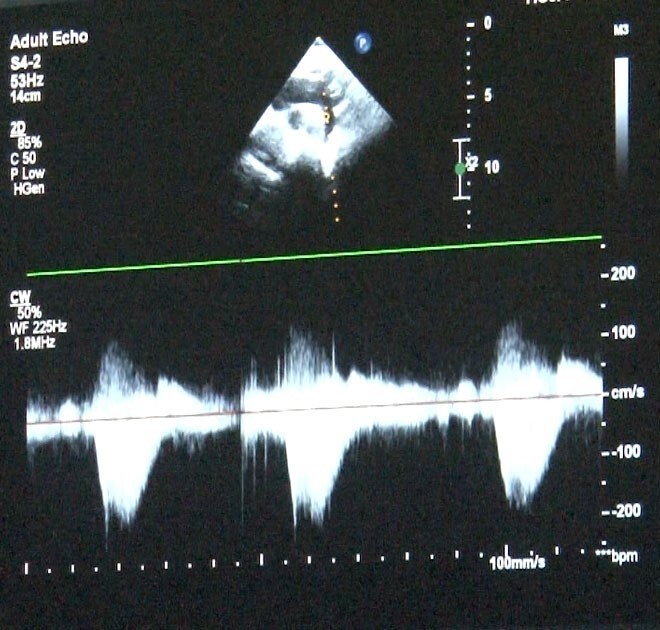

Erken tanı ve fetal ekokardiyografi

Kanuni Sultan Süleyman Eğitim ve Araştırma Hastanesi Çocuk Kardiyoloji Uzmanı Uzm. Dr. Damla Gökçeer Akbulut ve Sultangazi Haseki Eğitim ve Araştırma Hastanesi Çocuk Kardiyoloji Uzmanı Dr. Canan Yolcu erken tanının hayat kurtardığını aktarıyor. Fetal ekokardiyografi ile anne karnındayken doğumsal kalp hastalığı tespit edilebiliyor; böylece doğum sonrası erken müdahale şansı sağlanıyor. Uz. Dr. Gökçeer Akbulut, Sağlık Bakanlığı verilerine göre her yıl bin canlı doğumdan 8'inde doğumsal kalp hastalığı görüldüğünü hatırlattı.